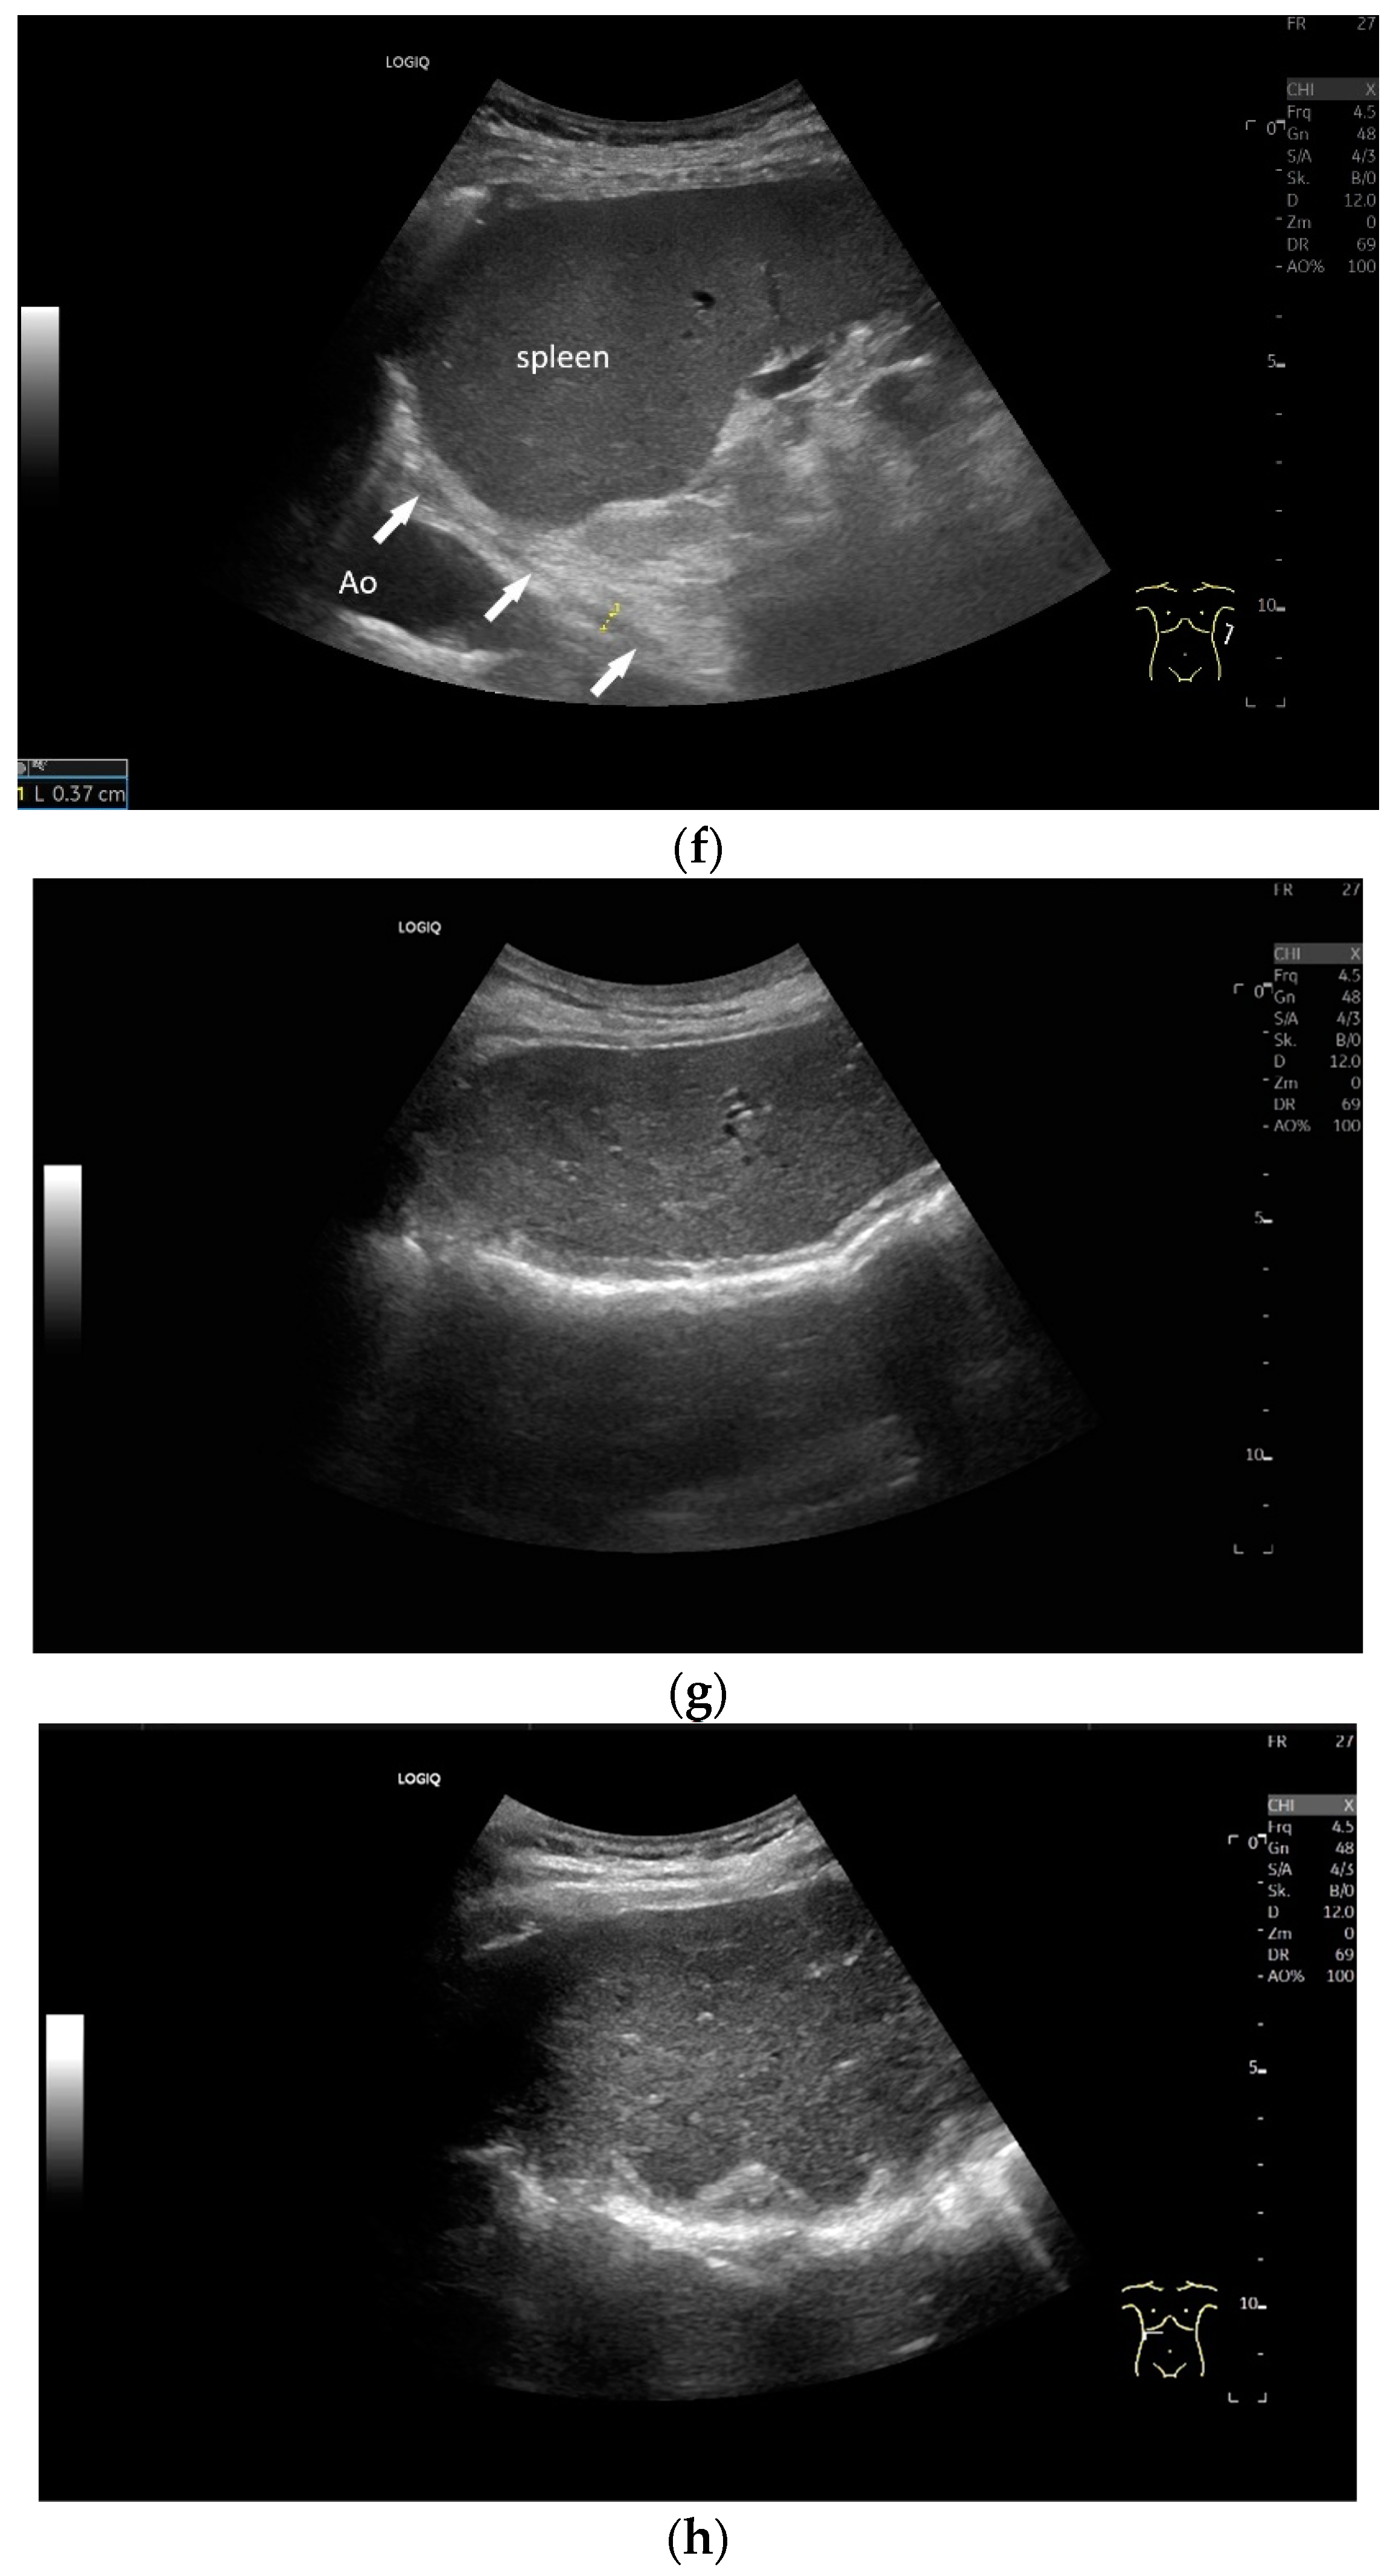

Subxiphoid: The diaphragm can be positioned directly subxiphoidally with a slightly sagittal transducer position on both sides next to the attachment to the sternum. The diaphragm limb can be demarcated to the right in the epigastrium in cross section between the aorta and the inferior vena cava. However, this is primarily of differential diagnostic importance, e.g., in relation to lymphomas, not for the actual assessment of the diaphragm (Figure 6).

If a diaphragmatic fistula is suspected in cases of ascitic decompensated liver cirrhosis and concurrent unilateral pleural effusion, it is possible to use intracavitary CEUS to demonstrate the passage of the contrast agent from one cavity to the other. However, this is off-label use and usually the last diagnostic step (Figure 8).